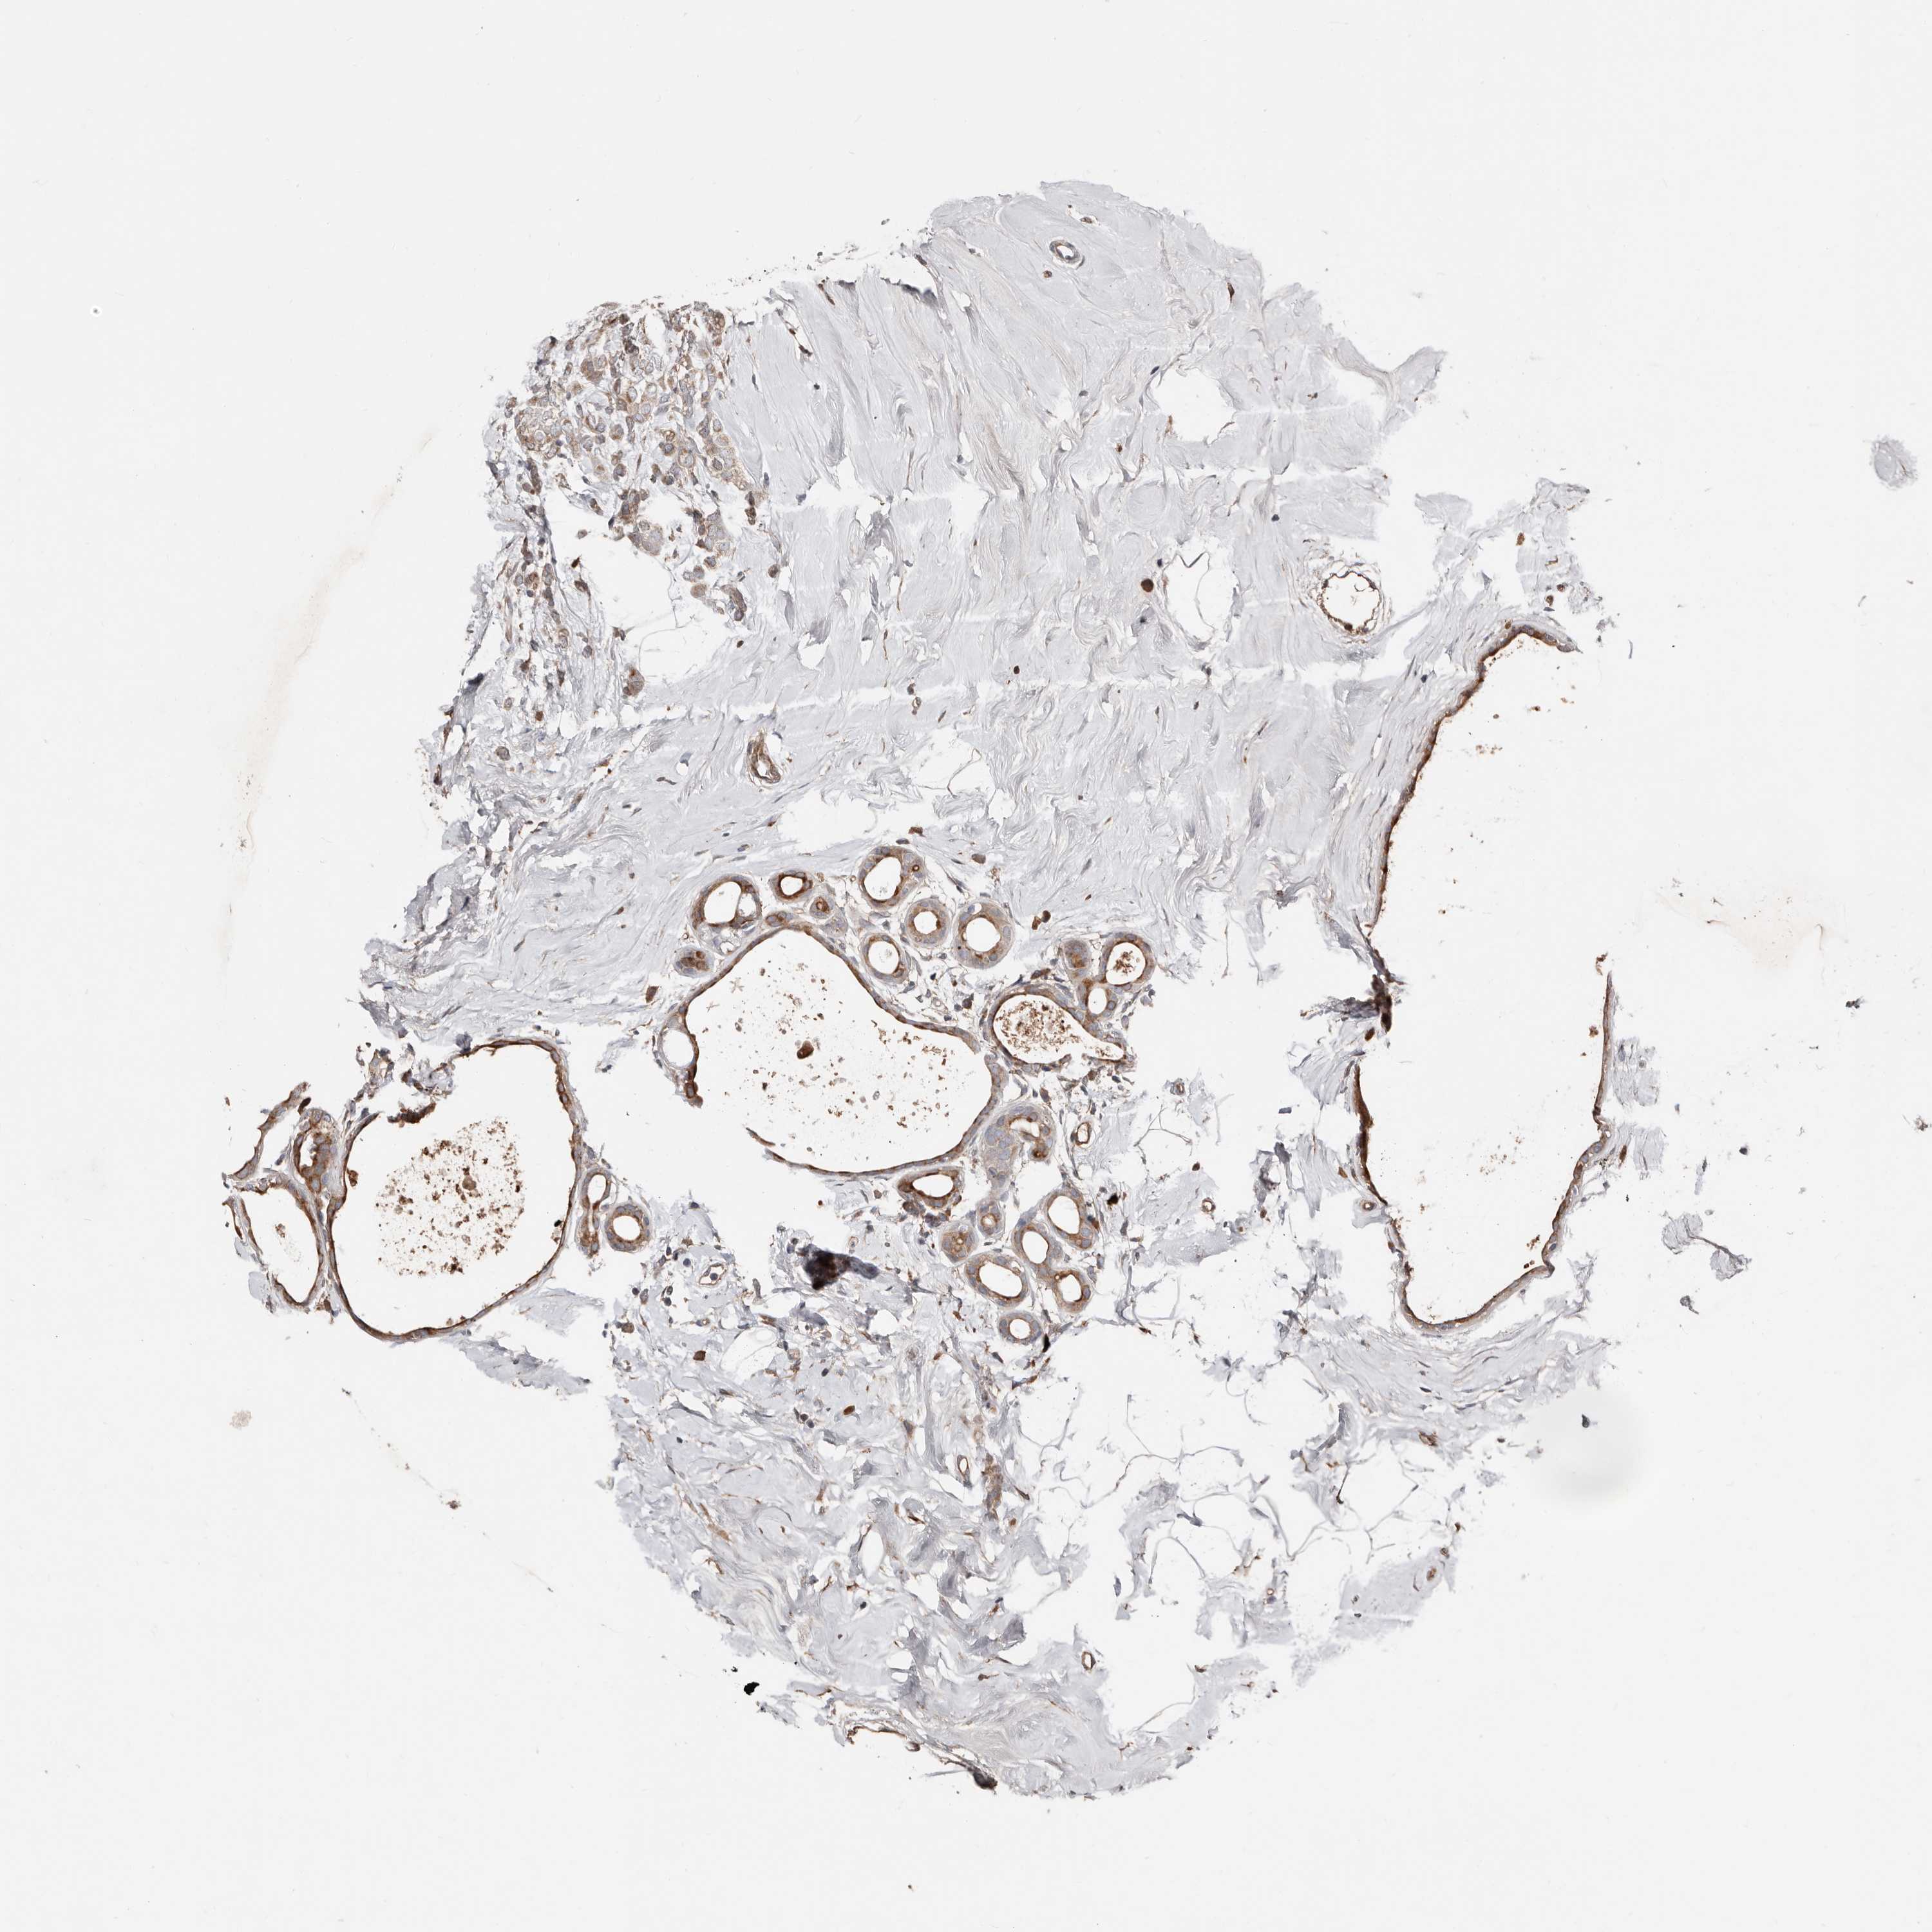

BRCA TCGA BRCA VALIDATION PROTEIN EXPRESSION

ANTIBODIES

AND

VALIDATION